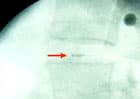

Röntgenaufnahme mit implantierter Sonde

Dr. Neef hat sich im Frühjahr 1996 eine Druckmesssonde in eine gesunde Bandscheibe an seiner WS (zwischen L4/5) einpflanzen lassen. Operateur Dr. Hoogland, Alpha-Klinik München. Die Messungen und Auswertungen wurden durchgeführt von Prof. A. Wilke vom Institut für Biomechanik der Universität Ulm (Caius Burri-Stiftung).

24 Stunden lang wurden BS-Drucke gemessen, unter allen möglichen Belastungen, auch im Schlaf, auch bei Chirotherapie an der WS. Das Team hatte noch viel mehr Messungen vor, aber leider rutschte die Sonde aus der Bandscheibe heraus. Der Unterschied in der Messtechnik war folgender: